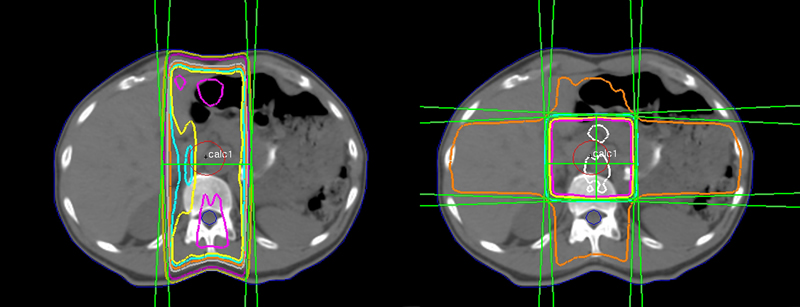

4-field Techniques

AP/PA is a simple pair of parallel-opposed beams with gantry angles of 0 and 180 degrees (assuming the patient is supine). A standard 4-field arrangement is a set-up of 4 equally spaced beams (AP, PA, right lateral, left lateral) with gantry angles of 0, 90, 180, and 270.